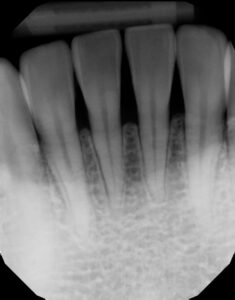

Final shaping was completed with the 3M® Soflex Coarse disc, followed by a final polish using Bioclear Magic Mix pre-polishing paste and the Bioclear Rockstar Polishing cup. (Figure 7) Rubber dam was removed, and the smile was evaluated for facial harmony. Adjustments were not needed for this patient as she was pleased with all aspects of her smile. (Figures 8-9) Post operative radiographs were taken to assess for excess composite and quality of technique and can be compared to the pre-operative x-rays. Post operative radiographs are useful for quality control. Notice how a smooth “infinity edge” can be created with the Bioclear matrices and technique. This is essential for a healthy tissue response. (Figures 10-11).

The matrix is removed from tooth #25, (Fig 24) and then #24 is injection molded. This to ensure a snug contact. The teeth are then rapidly sculpted together for sake of symmetry and efficiency. The final step is the Rock Star Polish. Invisible infinity edge margins are placed at mid-tooth. (Figs 25, 26) At one-year recall, the treated area is essentially bacteria and calculus-free, and the neighboring untreated embrasure is filled with calculus. The obvious health and quality of life of the treatment are a bonus to the esthetic benefits. (Fig 27) Pre- and post-operative radiographs demonstrate the imperceptible interface of composite to tooth and the void -free quality of the composite which is the goal if injection over-molded heated monolithic composite. (Figs 28, 29)